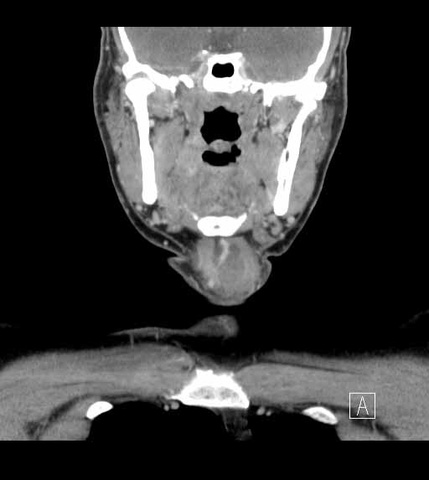

The patient was then prepped (including 1010 drape) and positioned for a central neck dissection thyroglossal duct cyst removal. Just to the left of midline, a large mass was palpated. A 15 blade was used to incise the skin with a horizontal marked incision and down onto the mass. Subplatysmal flaps were raised superiorly and inferiorly down to the area of the thyroid. We divided the straps midline. Of note just to the left of midline, the strap muscles were adherent to the cyst. Inferiorly the cricoid cartilage was identified as well as the thyroid. The mass was dissected around and it appeared to be in continuity with the pyraminal lobe and isthmus. The thyroid was divided to the right and then to the left and tied off with a 3-0 silk running stitch to permit resection of the isthmus in-continuity with the mass extending above.

We dissected the cyst and mass from an inferior to superior direction as it was removed from the cricothyroid muscles and thyroid cartilage up to the hyoid bone with care to avoid the superior laryngeal nerves. A small amount of strap musculateure was removed with the specimen where it was densely adherent on the left side.

The hyoid bone was identified with preservation of soft tissue about the central portion and isolation of the bone laterally. On the right side, just medial to the lesser cornua and used a Freer underneath to protect while we released the hyoid with the mighty bite. The left side was addressed in identical fashion, except that we were lateral to the lesser cornua. The dissection was carried superiorly with a cuff of muscle.